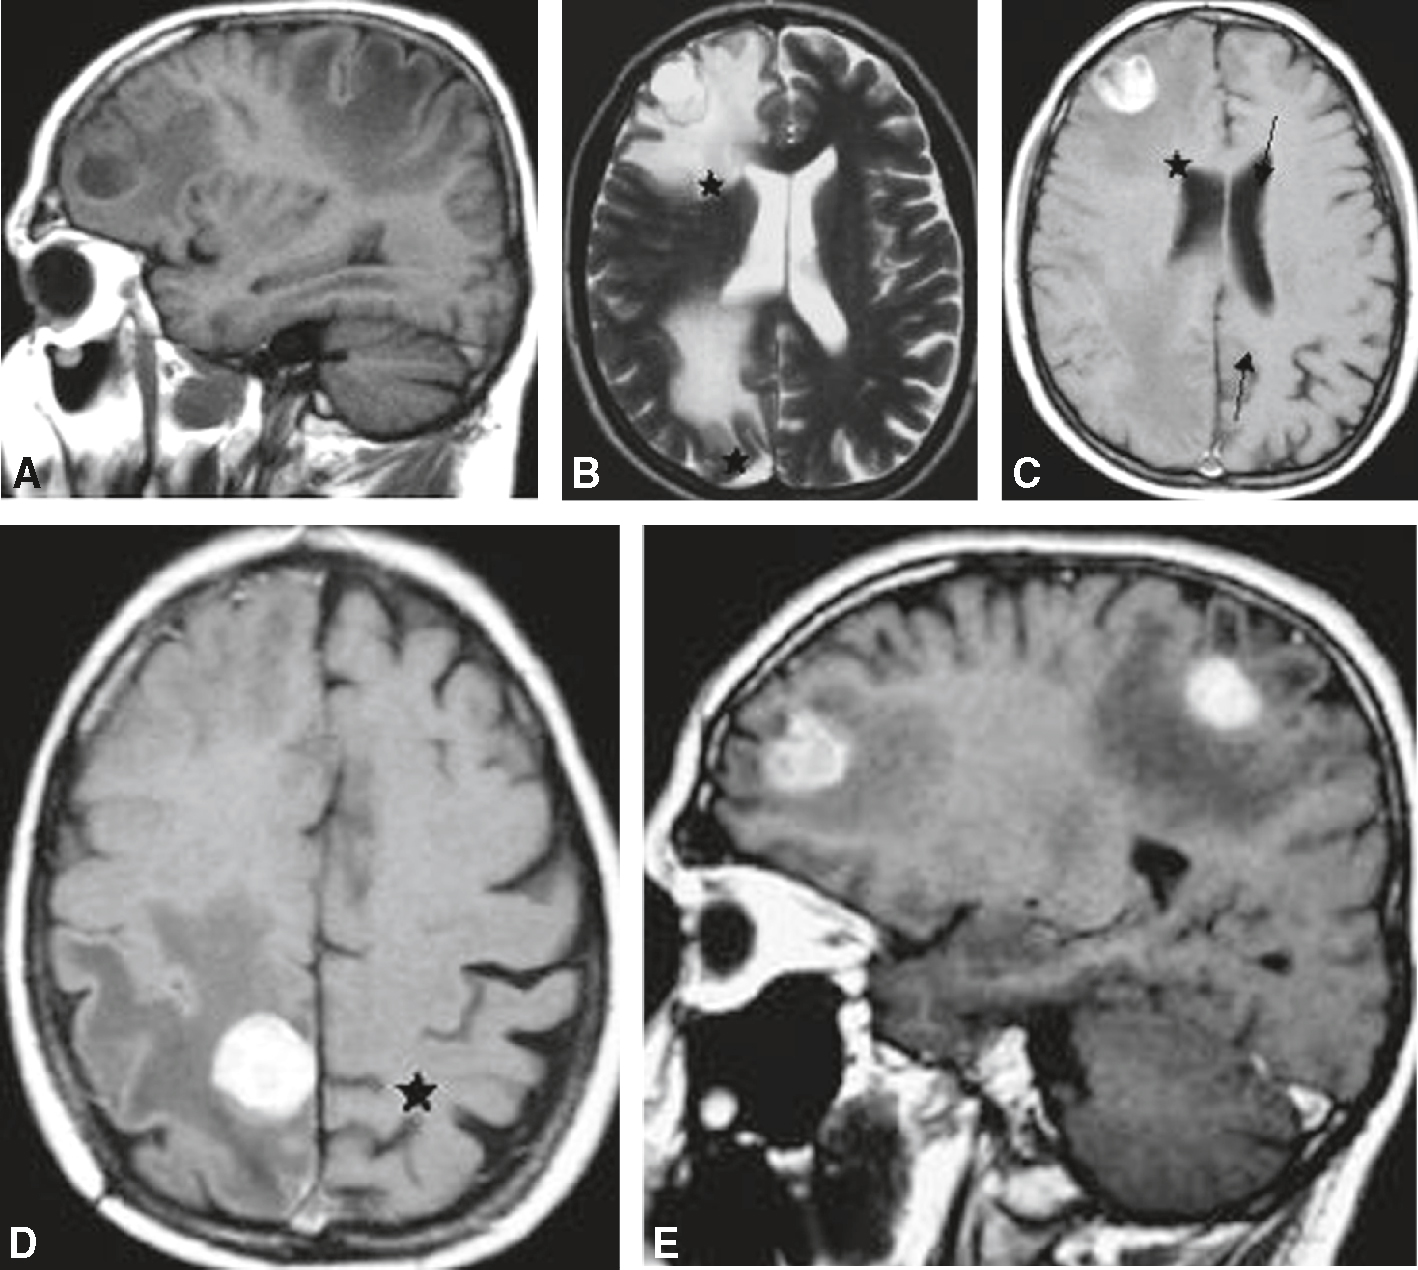

IRM cérébrale chez un patient de 26 ans présentant des crises épileptiques partielles depuis plusieurs mois. Volumineuse lésion paralimbique gauche en hypersignal T2 (A), en hypersignal hétérogène FLAIR (B), en hyposignal T1 (C), sans rehaussement pathologique (D), sans signes de néoangiogenèse : rCBV à 0,5 (E), avec un spectre tumoral : rapport choline/créatine (Cho/Cr) et choline/N-acétyl-aspartate (Cho/NAA) augmenté, présence de myo-inositol (ml) (F, G). A. T2, coupe coronale. B. FLAIR, coupe axiale. C. T1, coupe axiale. D. T1 avec injection de gadolinium, coupe axiale. E. Séquence de perfusion. F, G. Spectroscopie par résonance magnétique monovoxel à écho court 30 ms (F) et à écho long 135 ms (G).

IRM cérébrale chez une patiente de 67 ans, présentant des céphalées et des troubles phasiques d’installation rapide. Lésion bi-fronto-calleuse en hypersignal hétérogène T2 (A), en signal hétérogène FLAIR et œdème périlésion-nel important (B), en hyposignal T1 (C), avec rehaussement périphérique hétérogène et centre nécrotique (D), des signes francs de néoangiogenèse : rCBV à 3,6 (E), et un spectre tumoral : rapport choline/créatine (Cho/ Cr) et choline/N-acétyl-aspartate (Cho/NAA) augmenté, présence de lipides et lactates (F, G). A. T2, coupe coronale. B. FLAIR, coupe axiale. C. T1, coupe axiale. D. T1 avec injection de gadolinium, coupe axiale. E. Séquence de perfusion. F, G. Spectroscopie par résonance magnétique monovoxel à écho court 30 ms (F) et à écho long 135 ms (G).